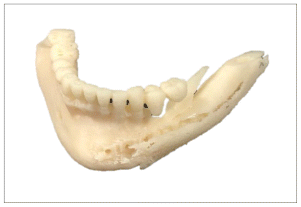

Subsequently, seven months later, on 10/17/12, she presented endodontic problems in the previously treated teeth and lost the second lower left molar after the revision, radiographic changes were seen in the panboramic X ray. (Figure 3) An incisional biopshy was taken,10 months 15/08/2013 based on the diagnosis of the biopsy, a CT scan was taken and a stereolithography model was developed for the surgery of the central ossifying fibroid by mandibular resection.

Due to the size of the lesion a mandibular titanium rod was placed to preserve the the lower portion of the mandible and part of the ascending ramus and condyle of the mandible (Figures 6,7,8) In the panoramic rx, the placement of the titanium rod can be seen to fix the ascending ramus with the condyle and the right side of the mandible with the resection to the level of the left lower canine (Figure 9).